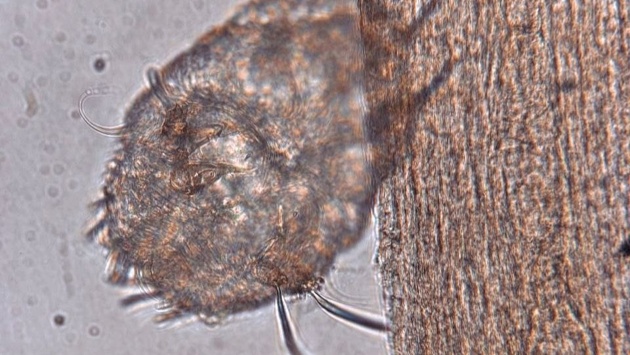

Недавно в Нижегородский филиал государственного научного центра дерматовенерологии и косметологии был направлен мужчина со странной клинической картиной. При осмотре между пальцами Илья Макарычев увидел подозрительное высыпание. Им оказался ход чесоточного клеща. Потом на соскобе лаборанты нашли и яйца, и самого возбудителя чесотки. Сейчас пациенту уже подобрали лечение.